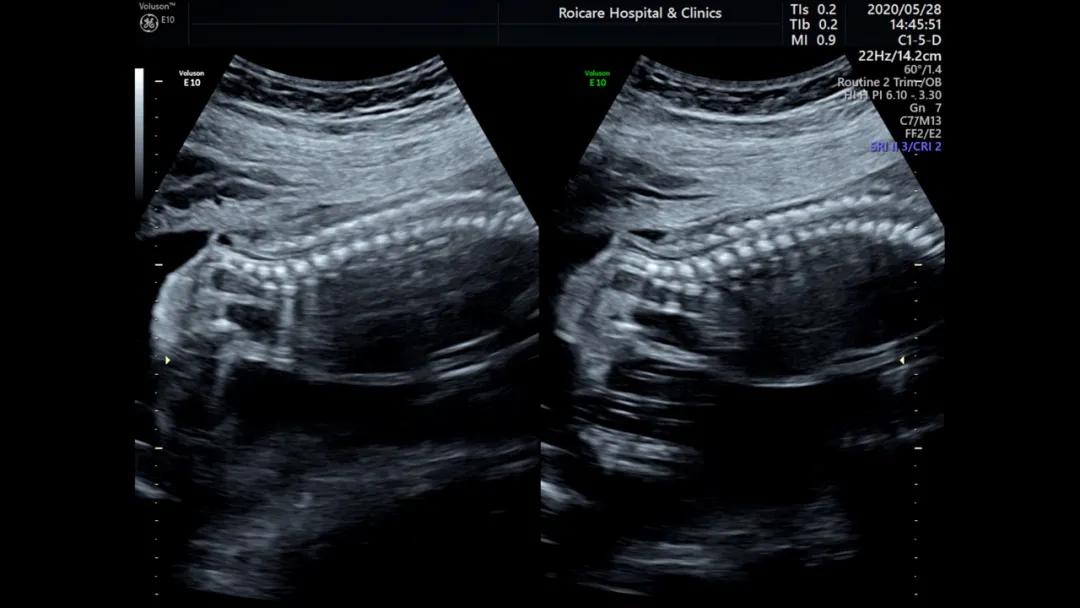

骶尾部脊柱裂伴脊髓脊膜膨出

开放性脊柱裂受累段脊髓神经损伤,可导致双下肢运动异常和大小便*禁失**;伴发脑室扩张或积水将影响运动、脑神经、认知功能。闭合性脊柱裂包括多种类型,即有包块型:脊膜膨出、脂肪脊髓脊膜膨出、脂肪脊髓裂、末端脊髓囊状膨出;无包块型:脊髓纵裂、终丝紧张、皮毛窦、尾端退化综合征等。